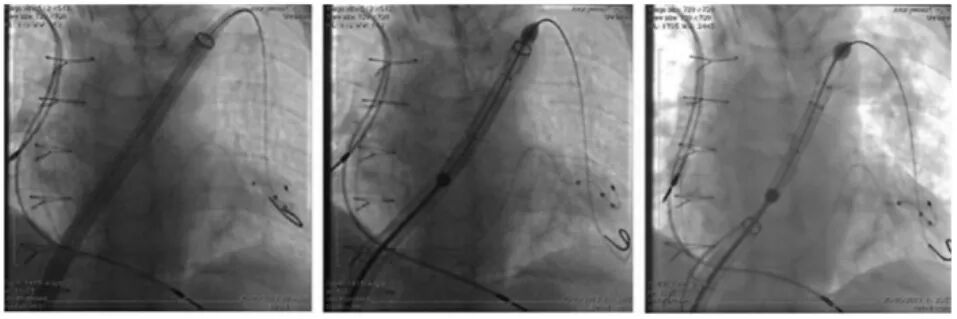

TAVl+Corpassing泊淮™ 大鞘

血管鞘组是什么器械百科丨Corpassing泊淮™ 导管鞘组_https://www.jmylbn.com_新闻资讯_第12张